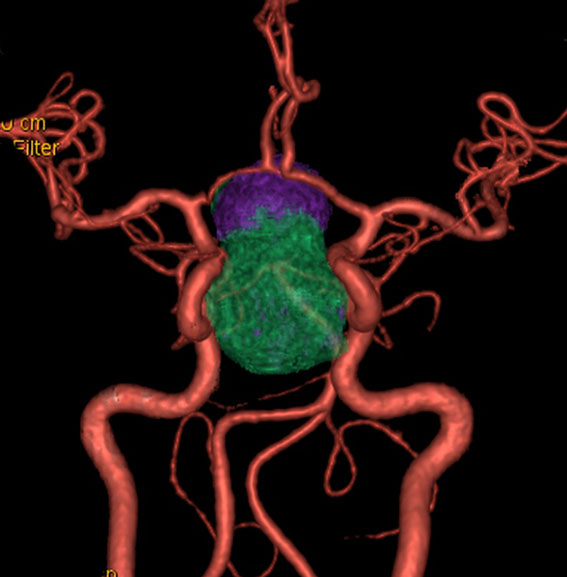

頭蓋骨を透して下垂体腺腫を見たものです。両目の間,頭の中心に緑色に塗ったのが下垂体腺腫です。頭蓋底の鼻腔の奥にあるともいえます。赤い色は動脈,青い色は静脈で,多くの血管に囲まれています。